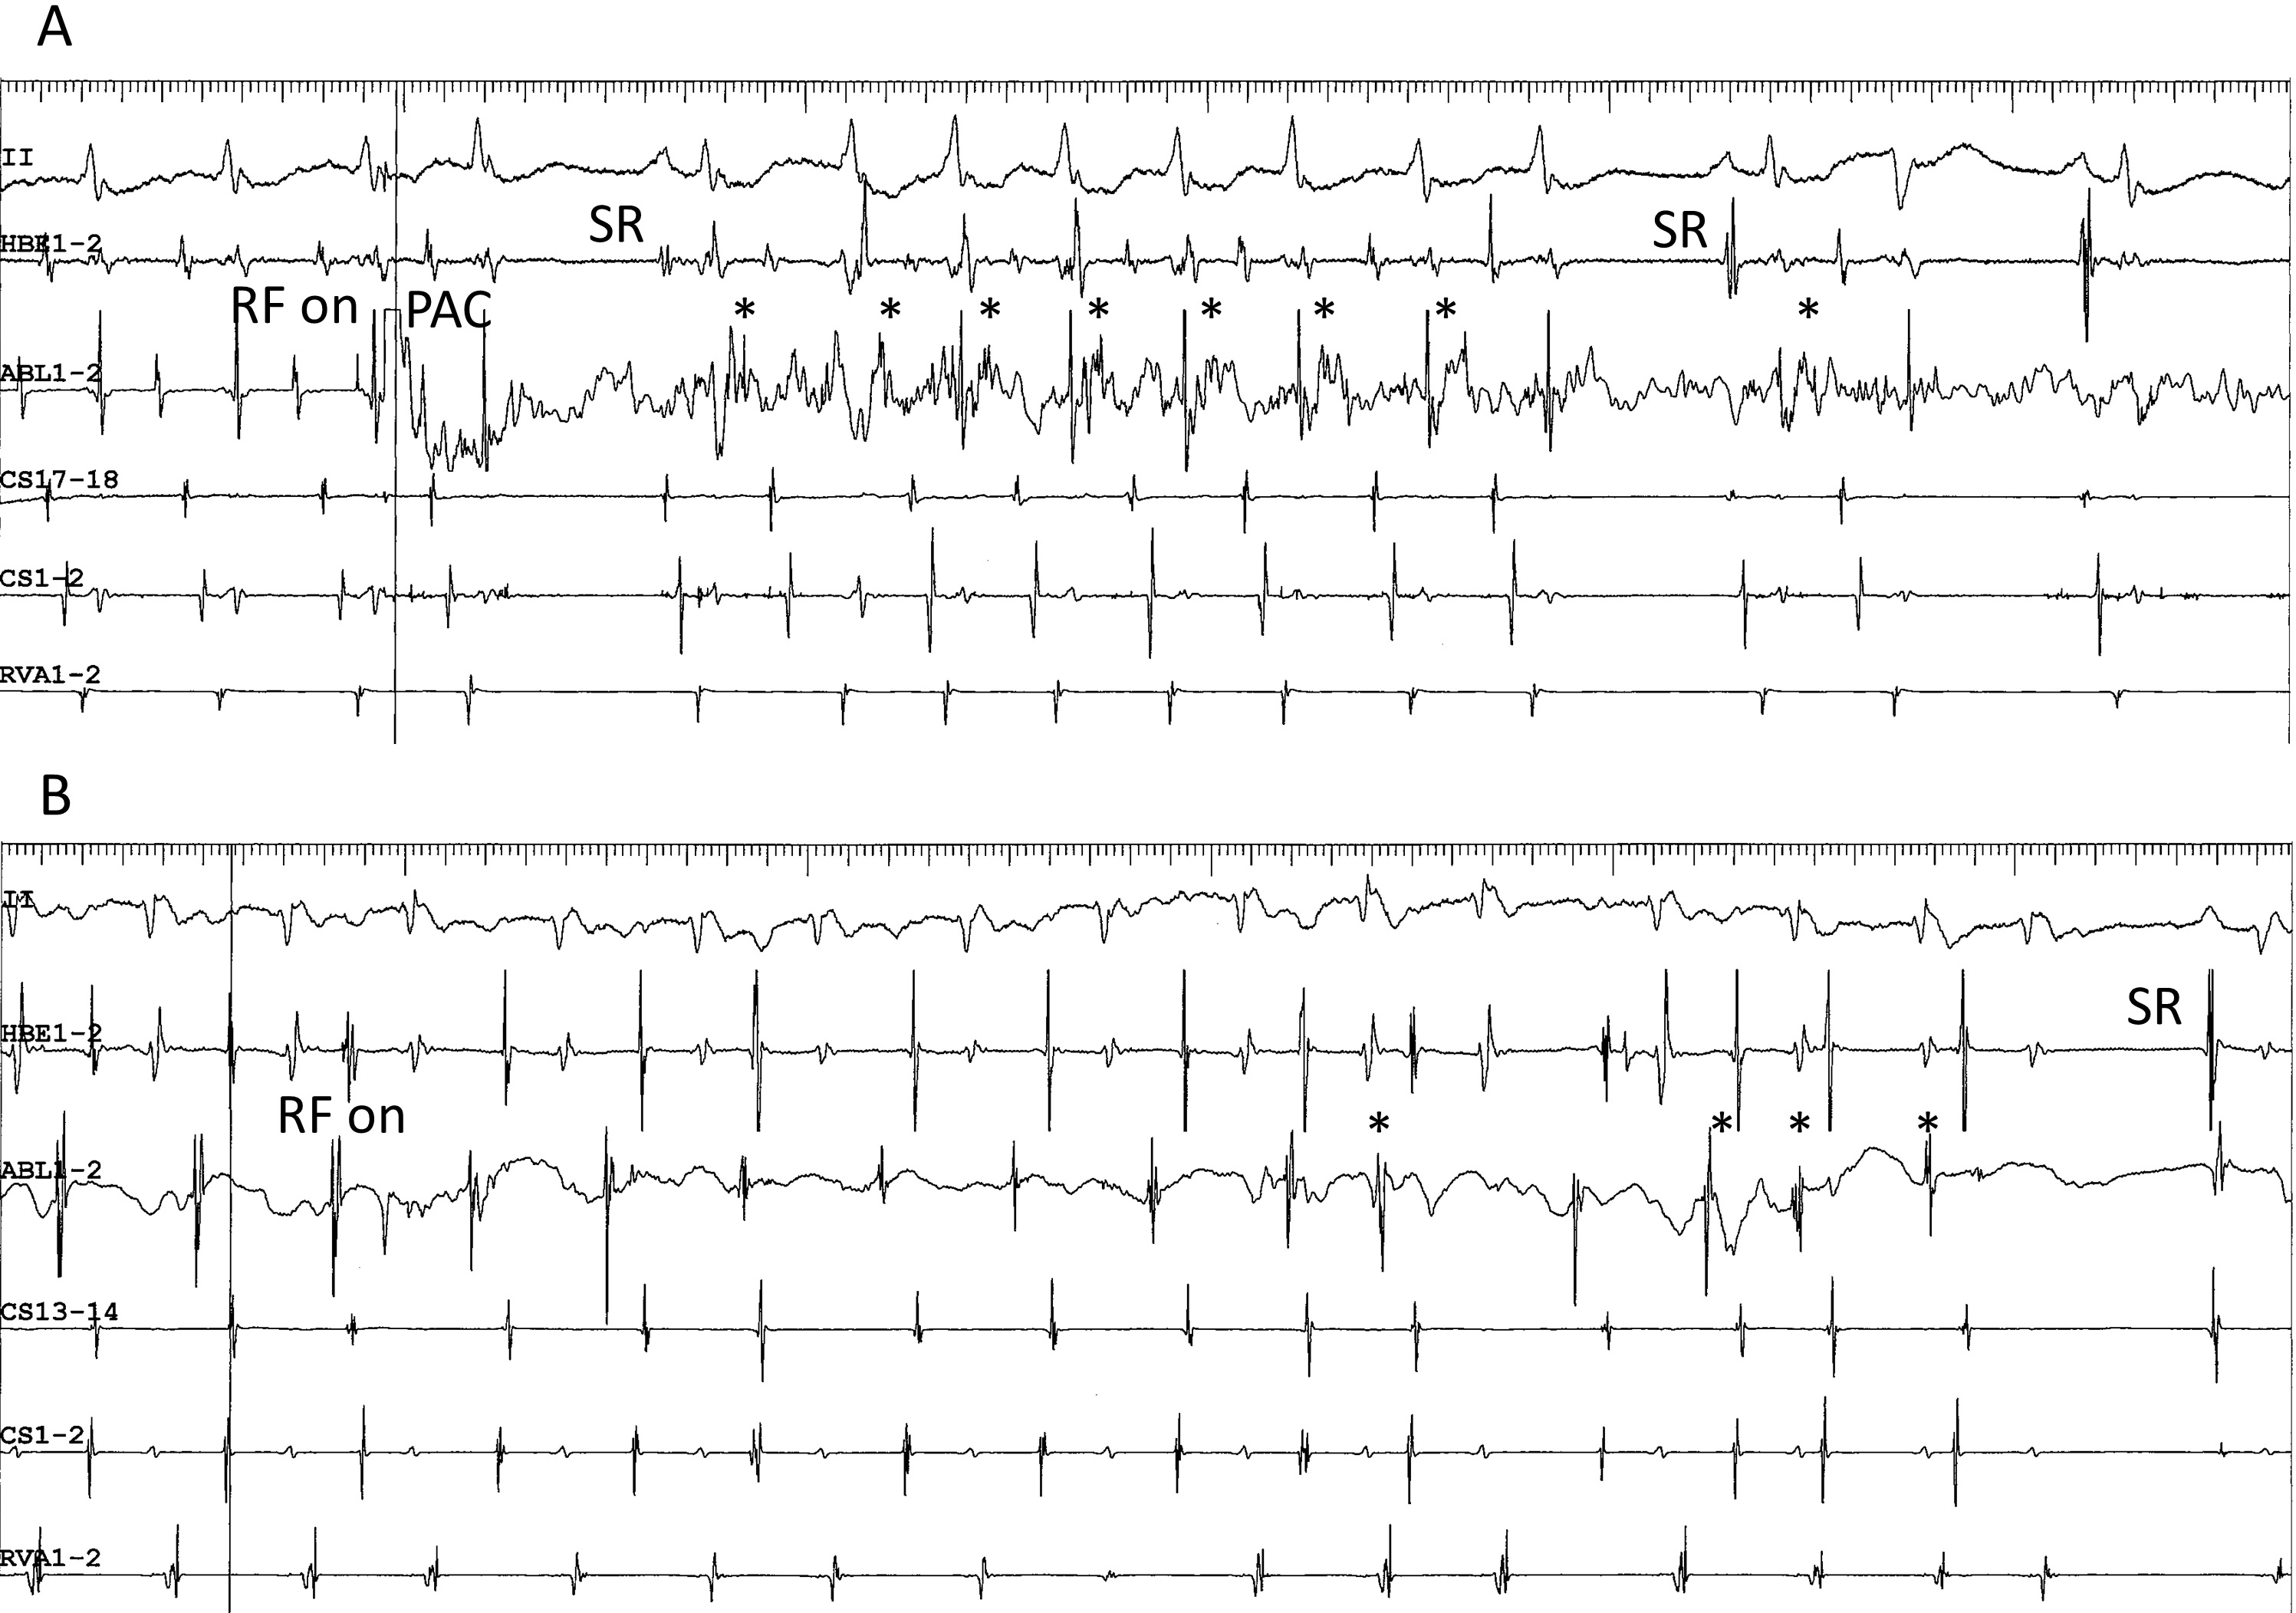

The second characteristic is the detection of low-frequency potentials preceding the local atrial activation, near the site of successful ablation. As described earlier, these potentials are found in the superoanterior or inferolateral fast-slow AVNRT (Fig. 4C,D, respectively) and may reflect retrograde activation across the SP [58]. Although the presence of prepotentials during adenosine-sensitive atrial tachycardia has not been reported previously [67, 80, 85], we have reproducibly detected low-frequency prepotentials within a localized area near the site of earliest atrial activation during an atrial tachycardia originating from the inferolateral right atrium, along the tricuspid annulus (Fig. 4E). Yamabe et al. [86] have described low-frequency, late potentials following local atrial activation during sinus rhythm, probably reflecting a delayed activation of the tachycardia origin, near the site of successful ablation, in patients presenting with atrial tachycardia originating from the tricuspid annulus. The presence of these potentials suggests a slowly conducting, common arrhythmogenic substrate of these tachycardias. The third characteristic is the development of accelerated atrial ectopic activity during delivery of radiofrequency energy. This is often observed during ablation of right atrial, superior, superoanterior (Fig. 7A) and inferolateral SP, as described earlier. Moreover, in contrast to previous reports [80, 86], we have also observed it during ablation of atrial tachycardia originating from the tricuspid annulus (Fig. 7B). This activity may be caused by heating of the AV nodal transitional cells present in these tissues [63]. The fourth characteristic is the occurrence of multiple shifts of the site of earliest atrial activation during tachycardia with each radiofrequency application. As described earlier, this phenomenon is occasionally observed after the ablation of superoanterior or inferolateral right atrial SP, or of atrial tachycardia originating from the tricuspid annulus [69]. Collectively, these anatomical, electrophysiological and pharmacological characteristics suggest that the AV node-like tissue distributed around the tricuspid annulus is the arrhythmogenic substrate shared by these tachycardias.

Fig. 7.Development of accelerated ectopic atrial cycles during radiofrequency delivery. (A) Accelerated ectopic atrial rhythm (asterisks) developing immediately after radiofrequency energy was delivered (RF on) during an ongoing superoanterior-type of fast-slow AVNRT, in the same patient as shown in Fig. 4C. The tachycardia is terminated by a premature atrial complex (PAC) immediately after the delivery of radiofrequency energy. (B) ATP-sensitive atrial tachycardia originating from the inferolateral right atrium along the tricuspid annulus, followed by return to sinus rhythm (SR) in the same patient as in Fig. 4E. II, surface electrocardiogram lead II; HRA1-2, high right atrium; HBE1-2, His bundle electrogram; CS13-14 to 1-2, proximal to distal coronary sinus; RVA1-2, right ventricular apex.